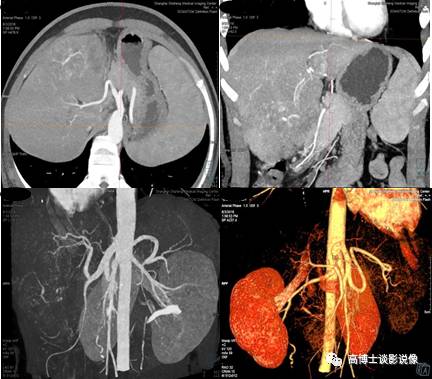

五、肝脏肿瘤血管CTA术前评估

动脉期进行MIP重建,显示肝脏肿瘤的供血动脉特点、供血类型,显示有无动静脉瘘形成。采用去骨的VR图像,显示肝动脉及肠系膜上动脉的整体解剖形态,显示有无解剖变异及其类型。